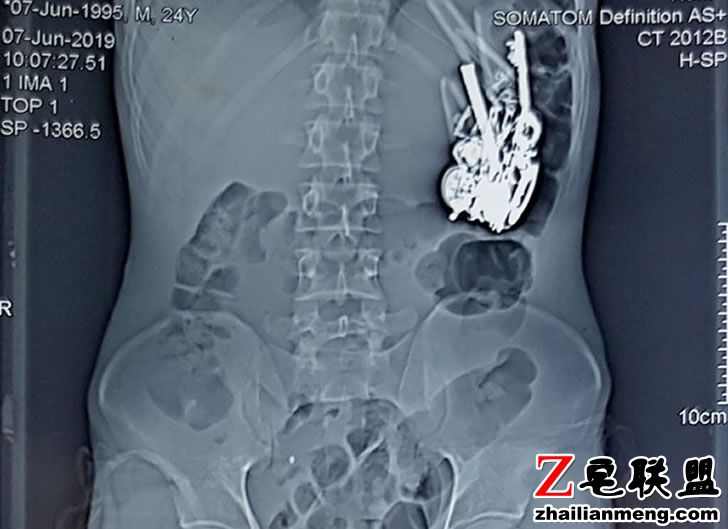

又是印度,来自拉贾斯坦邦 Udaipur 有一名24岁青年日前因为腹痛、长期慢性呕吐就医,结果医生帮他进行腹部、肠道扫描后,发现他的腹中内竟有80多种金属及其他材质异物,吓得立刻进行手术将异物全部取出。

当地医院的外科医生 Dr Sharma 表示,病患就医时自称有长期慢性呕吐、腹痛、食欲不振等症状,因此他就替对方进行腹部、肠道的电脑断层扫描及 X 光扫描,结果就发现病患的胃部积了一堆的异物,手术后进一步发现是80多种金属及玻璃、木质等材质的异物。

Sharma 取出男子体内所有异物后相当傻眼,因为里头包含各种非常离奇的物品。

像是硬币、吸食大麻用的短陶管、指甲剪、一些玻璃制品、钥匙、钥匙圈、项炼、发夹、刀片、安全别针和眼镜领带夹,而且一些铁器外观有明显的生锈痕迹,因此男子应该已经吞食有一段时间了。